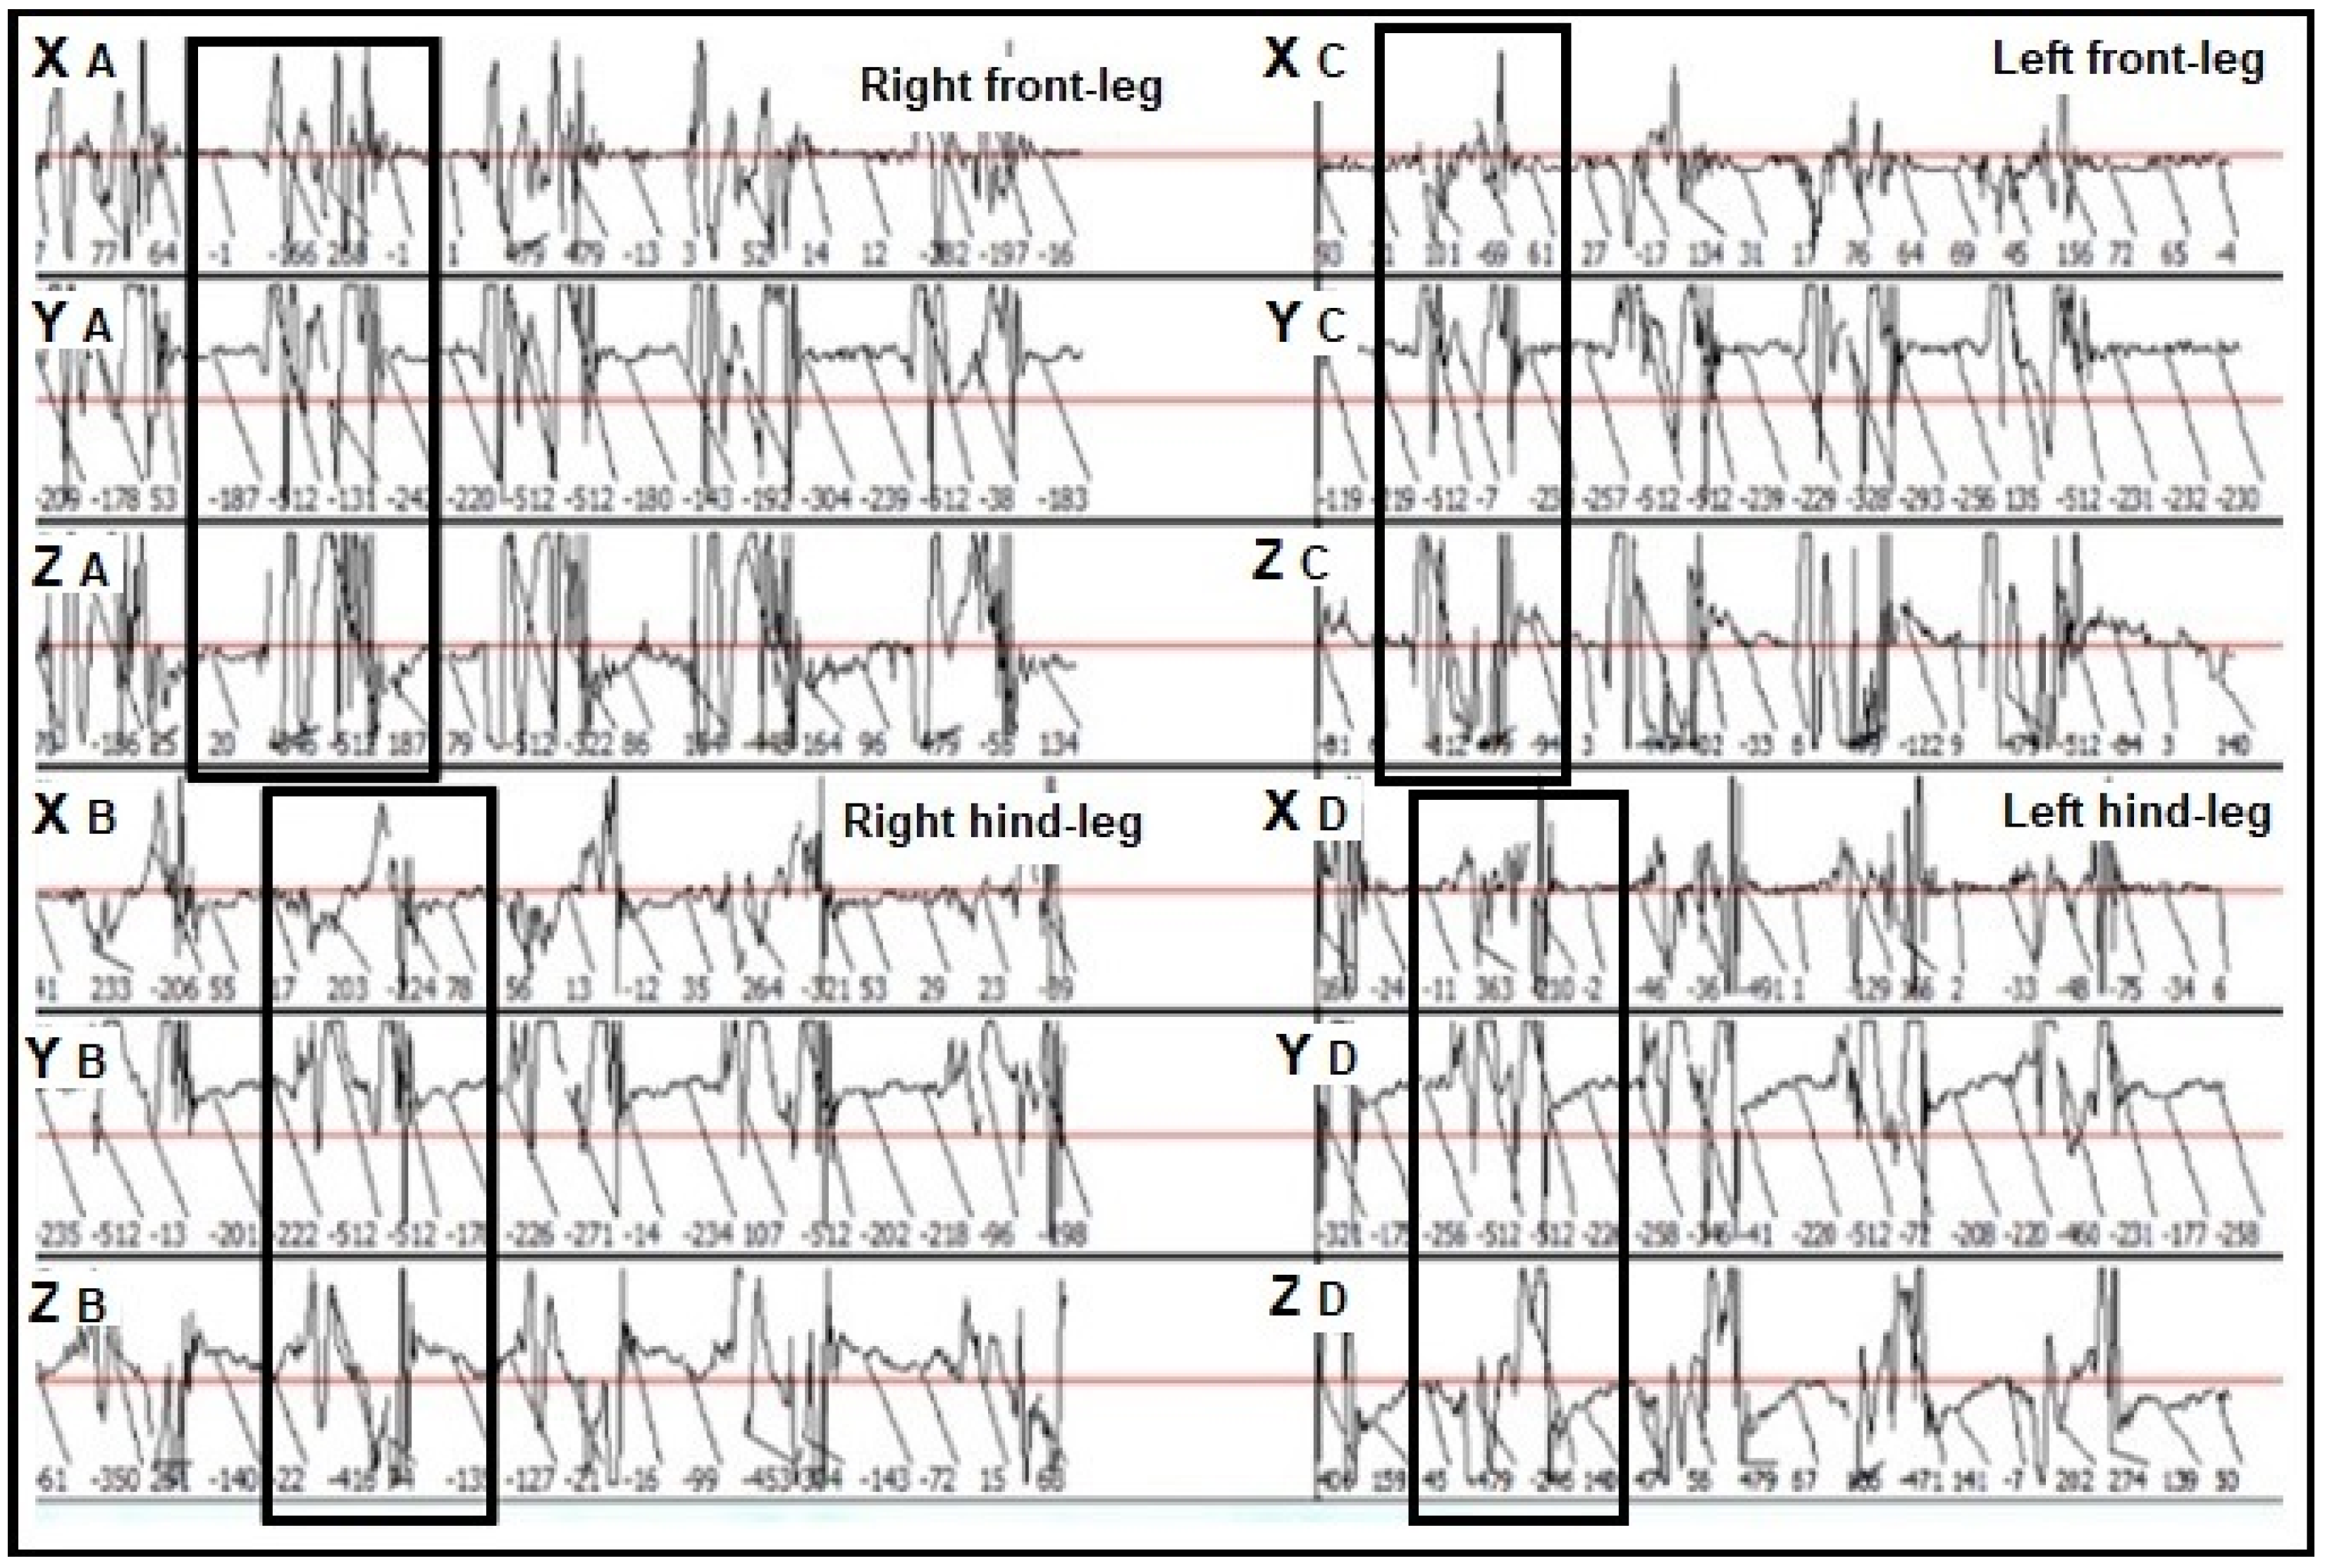

3.1. Descriptive Statistics for the Mean Impulse Numbers Recorded in the Lame and Sound Contralateral Legs of the Assessed Horses